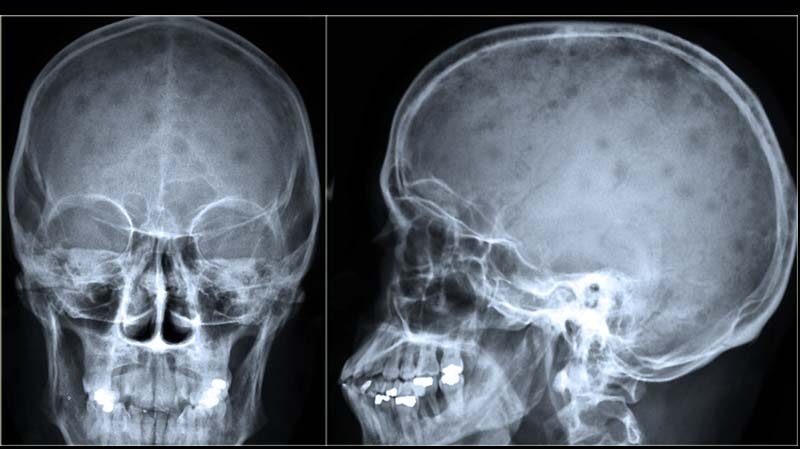

En muchos casos, el mieloma múltiple no presenta síntomas evidentes en sus etapas iniciales, por lo que su diagnóstico puede surgir de manera accidental, a partir de estudios de rutina o durante la investigación de otras afecciones. Sin embargo, algunos signos de alerta que podrían indicar la presencia de la enfermedad incluyen dolor óseo persistente, anemia (bajo recuento de glóbulos rojos), niveles elevados de calcio en sangre, insuficiencia renal e infecciones recurrentes.